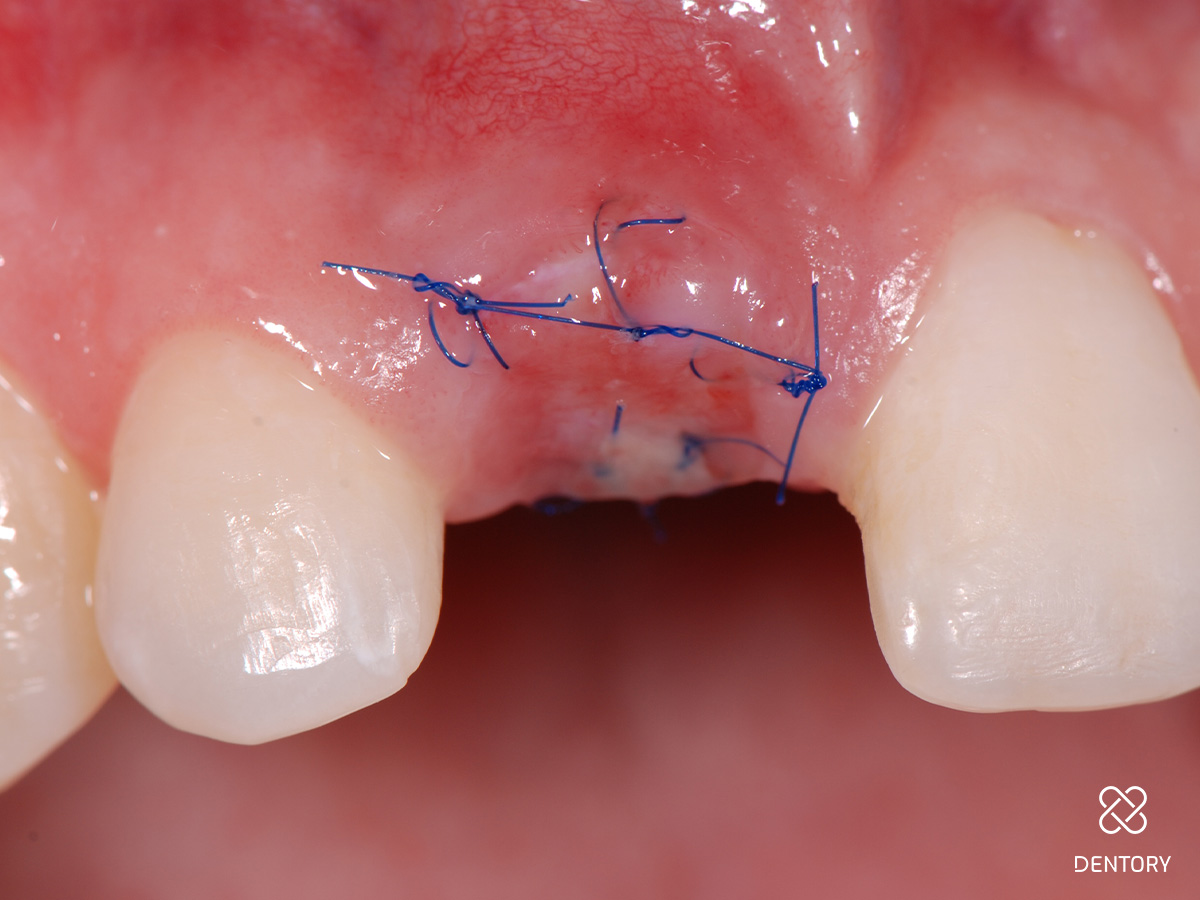

Abbildung 10

Eingenähter Punch vom seitlichen Gaumen: Die Entnahme kann im Prämolaren- oder Tuberbereich erfolgen.

Abbildung 11

Das Transplantat kann mit wenigen Mikronähten fixiert werden; die Passung sollte wie bei einem Korken mit etwas Druck sein.